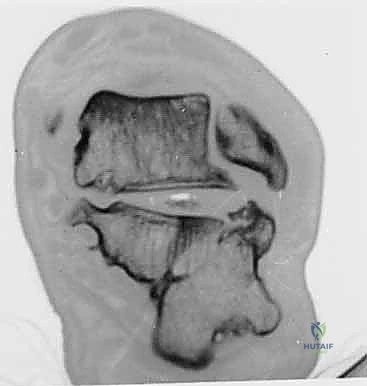

تُظهر الصورة أعلاه فحصاً بالأشعة المقطعية يوضح مدى تعقيد الكسر الأولي والإزاحة التي تحدث، مما يسلط الضوء على التشريح الفوري بعد الإصابة والذي يمهد لسوء الالتئام إذا لم يُعالج بدقة.

3. التصوير المقطعي المحوسب (CT Scan) مع إعادة البناء ثلاثي الأبعاد (3D Reconstruction)

لا يمكن التخطيط لجراحة تصحيح سوء التئام عظم العقب بدون أشعة مقطعية. توفر الأشعة المقطعية رؤية دقيقة للتشريح العظمي المشوه، وتحدد بدقة مكان الانحشار الشظوي، حالة الأسطح المفصلية، ومسار الأوتار. التخطيط ثلاثي الأبعاد يسمح للجراح ببناء نموذج افتراضي للقدم وتحديد أماكن القطع العظمي المطلوبة بدقة مليمترية قبل الدخول إلى غرفة العمليات.